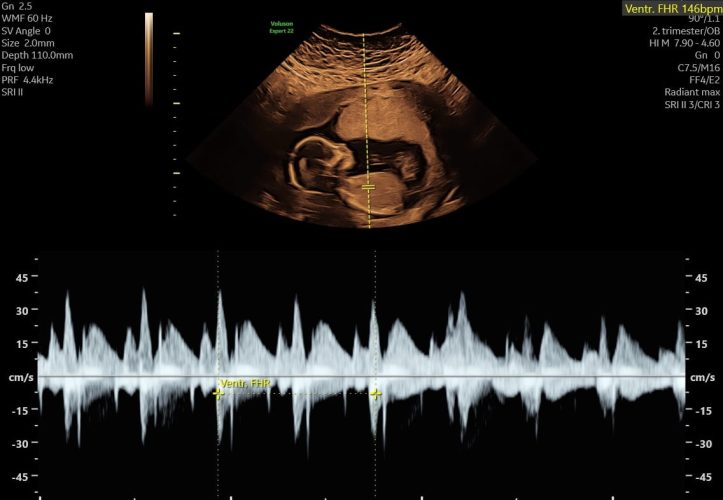

Hvordan ses kønnet på ultralydsbilledet?

Køn vurderes ved at se på de ydre kønsorganer ved ultralyd. I de tidlige uger ligner de hinanden meget – både hos drenge og piger udvikler de sig fra den samme grundstruktur (kønsknoppen). Senere i graviditeten bliver forskellene tydeligere.

Hvad jordemoderen kigger efter

Vurderingen sker ud fra kønsorganernes vinkel og form:

- Pige: Tre parallelle linjer mellem benene (de såkaldte ”hamburger-linjer” eller ”tre linjer”) – kønsknoppen peger nedad eller ligger fladt mod underlivet.

- Dreng: En lille fremspringende struktur – ofte beskrevet som en ”skildpadde” eller ”snegl” – hvor penis-knoppen peger opad i en tydelig vinkel.

Selv ved en god scanning kan kønnet være svært at vurdere – især hvis barnet ligger med benene samlet, navlestrengen ligger over kønsområdet, eller fostret bevæger sig. Vurderingen er sjældent et simpelt ”ja eller nej” – det er et fagligt skøn baseret på det vi kan se.